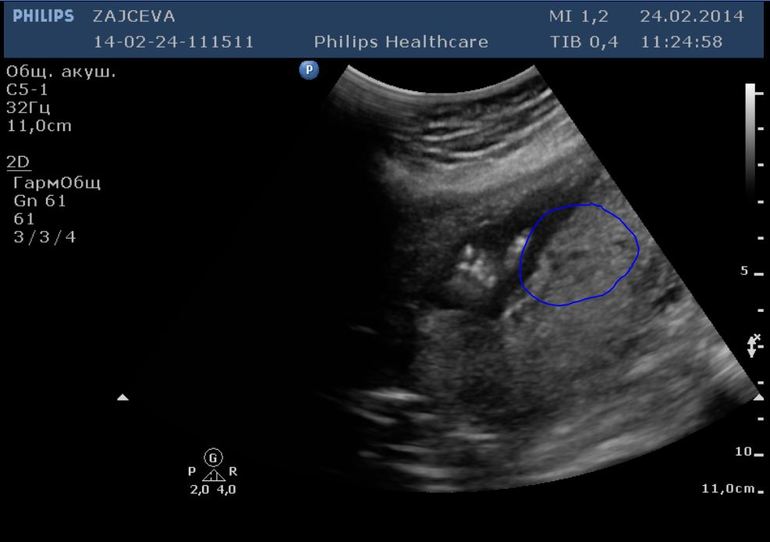

Побежала к Г. Мне подтвердили беременность. Но я волновалась из-за этого 1 дня кровотечения. И вообще не верилось. Поэтому сходила на УЗИ. Там поставили срок 6,5 недель. Показали точечку на мониторе... Дали сердечко послушать... Вот это счастье!